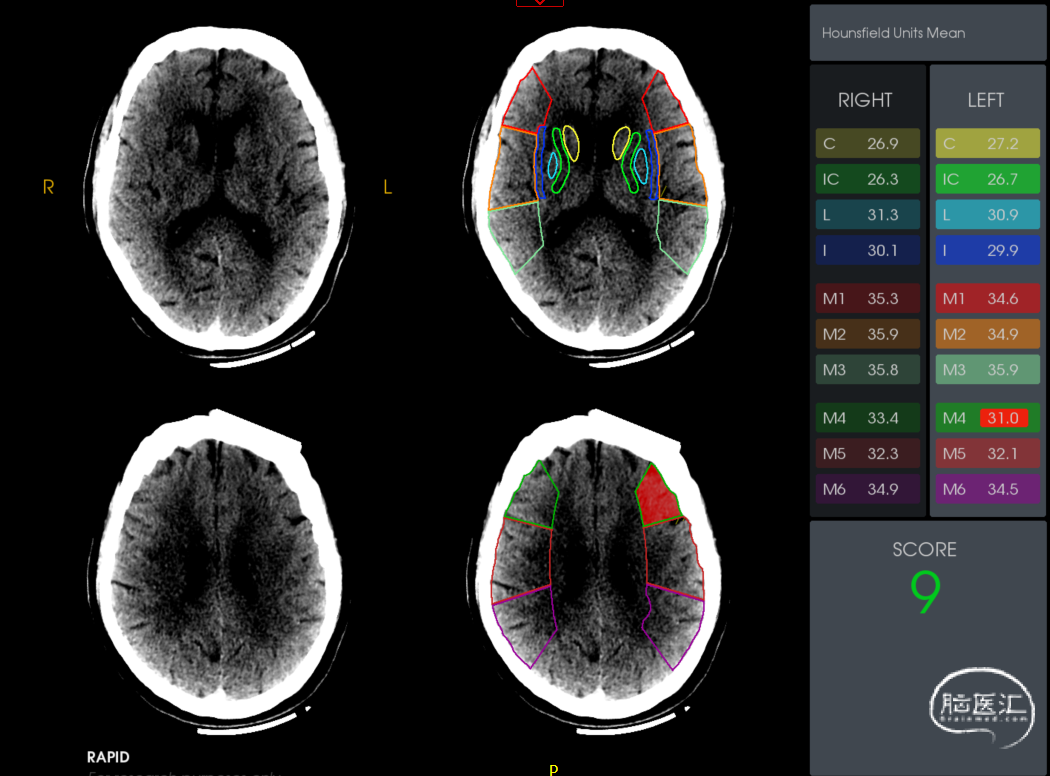

NIHSS:11分

ASPECTS 9分

缺血体积124ml,梗死核心25ml